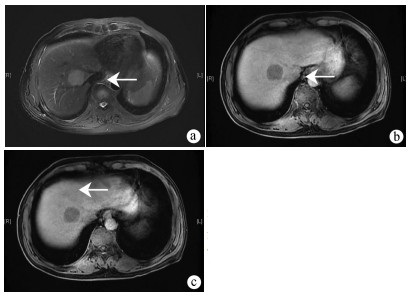

Consensus on imaging techniques and diagnostic criteria for hepatitis B virus related early hepatocellular carcinoma

Radiology of Infection Sub-branch, Radiology Branch, Chinese Medical Association, Committee on Radiology of Infection, Radiology Branch, Chinese Medical Doctor Association, Radiology Committee on Infectious and Inflammatory Disease, Chinese Research Hospital Association, Radiology of Infection Branch, Working and Treating Committee of HIV/AIDS and STD Association, Radiology of Infectious Disease Management Sub-branch, Infectious Disease Management Branch, Hospital Management Association in China, Beijing Imaging Diagnosis and Treatment Technology Innovation Alliance

2021, 37(4): 787-791. DOI: 10.3969/j.issn.1001-5256.2021.04.013

Abstract(1427) HTML (513) PDF (4471KB)(236)

Abstract:

The pathological diagnostic criteria for early hepatocellular carcinoma(eHCC)have been updated in 2009, but the imaging diagnostic criteria for eHCC have not yet been established by domestic or foreign academic organizations. Promoted by Radiology of Infection Sub-branch, Radiology Branch, Chinese Medical Association, associating with Committee on Radiology of Infection, Radiology Branch, Chinese Medical Doctor Association; Radiology Committee on Infectious and Inflammatory Disease, Chinese Research Hospital Association; Radiology of Infection Branch, Working and Treating Committee of HIV/AIDS and STD Association; Radiology of Infectious Disease Management Sub-branch, Infectious Disease Management Branch, Hospital Management Association in China; Beijing Imaging Diagnosis and Treatment Technology Innovation Alliance, this consensus was formed under the efforts of more than 40 experts from more than 10 domestic provinces and cities, so as to help related professional doctors in diagnosis of eHCC.